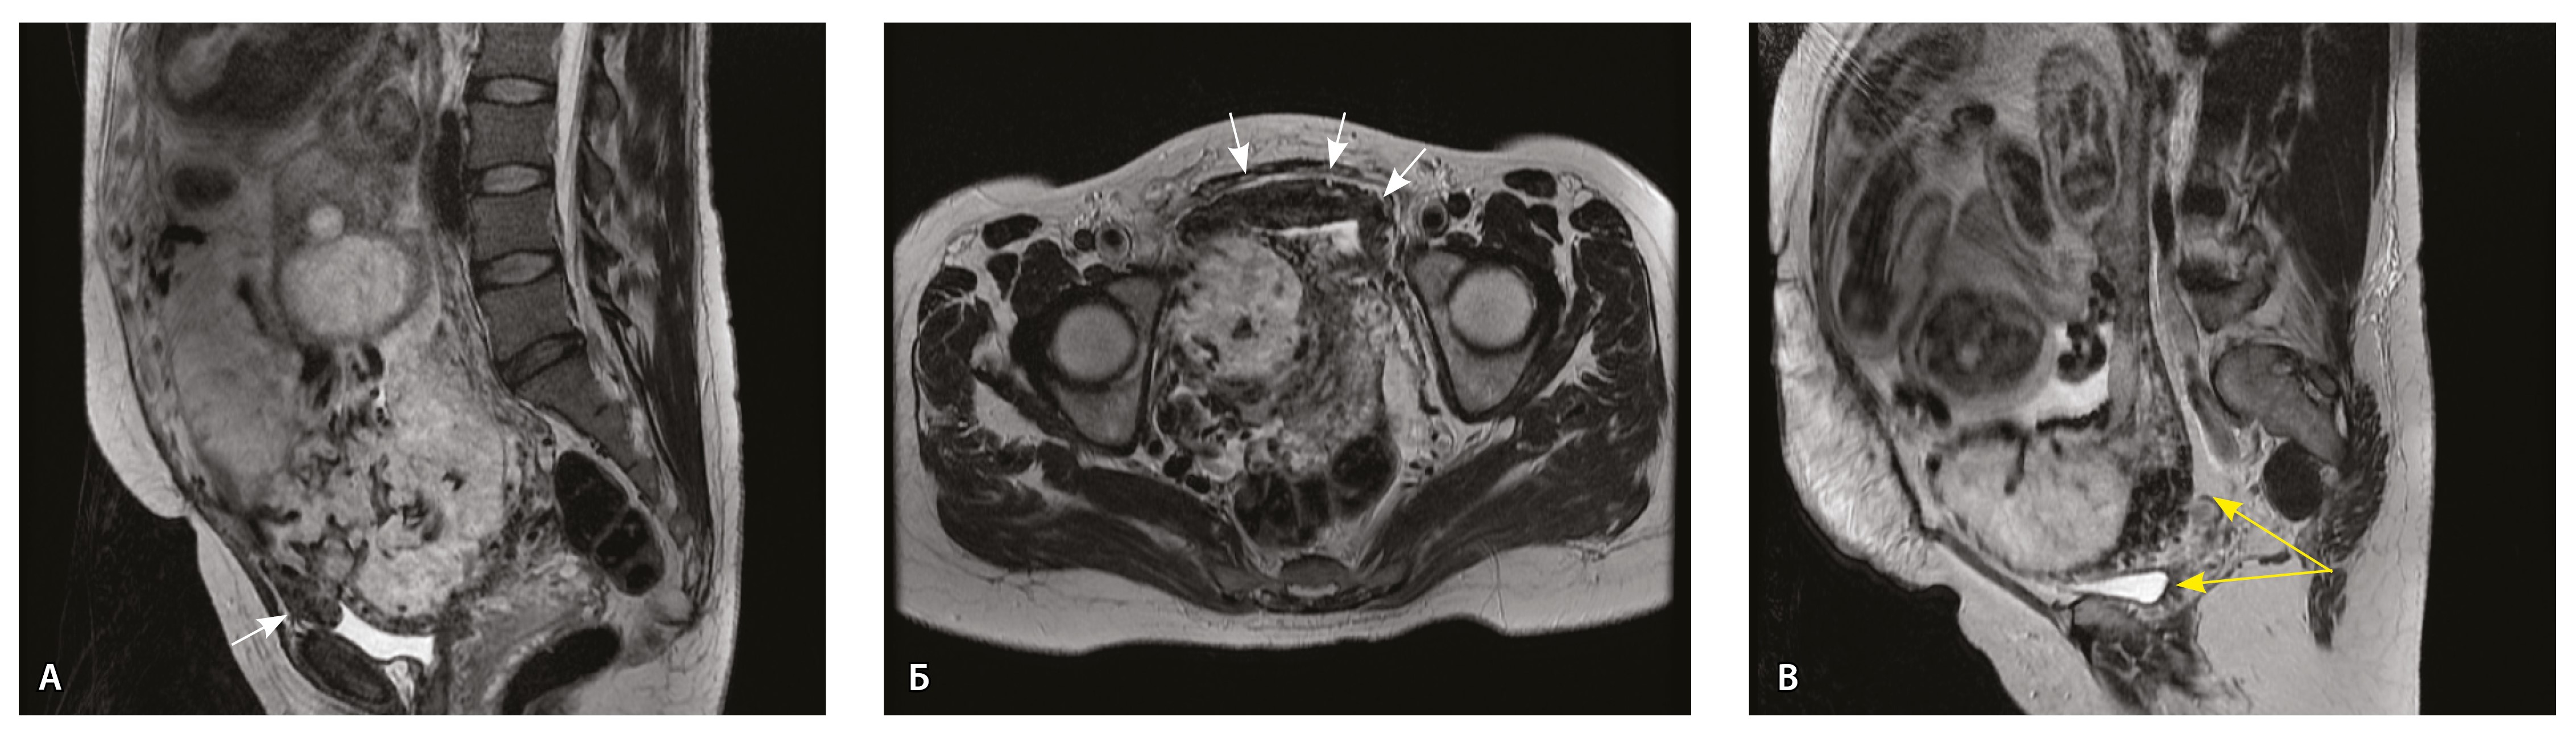

Сосуды 3-го типа. Внутриматочная гиперваскуляризация с дефицитом толщины миометрия, преимущественно сосуды срединного слоя, аналог pl. increta PAS 2, гестационная перестройка радиальных артерий (рис. 7).

Рис. 7. Беременность 34 недели, pl. increta, PAS 2 по FIGO. На магнитно-резонансных томограммах в режиме Т2-взвешенного изображения в сагиттальной (A, Б) и фронтальной (В) плоскостях определяется внутриматочная гиперваскуляризация с наличием многочисленных сливающихся сосудов в толще стенки матки, в области плацентарной площадки (белые стрелки); в нижнем маточном сегменте – выраженное истончение стенки матки, рубца от кесарева сечения с формированием маточной грыжи (желтые стрелки)

При pl. increta наличие патологических сосудов на изображениях МРТ связано с неполной гестационной перестройкой радиальных артерий, расположенных в срединном слое миометрия. Так, при окраске по Маллори они определяются как сжатые комплексы артерий среднего калибра, с частичным замещением внутренних слоев стенки матки, темно-красными фрагментами плодного фибриноида. На серийных срезах видно, что в этой артерии присутствует достаточное количество инвазивного цитотрофобласта (маркер цитокератин 8), но предыдущий срез подтверждает замещение мышечной оболочки фиброзной тканью как в стенке радиальной артерии, так и в периартериальном пространстве (рис. 8).